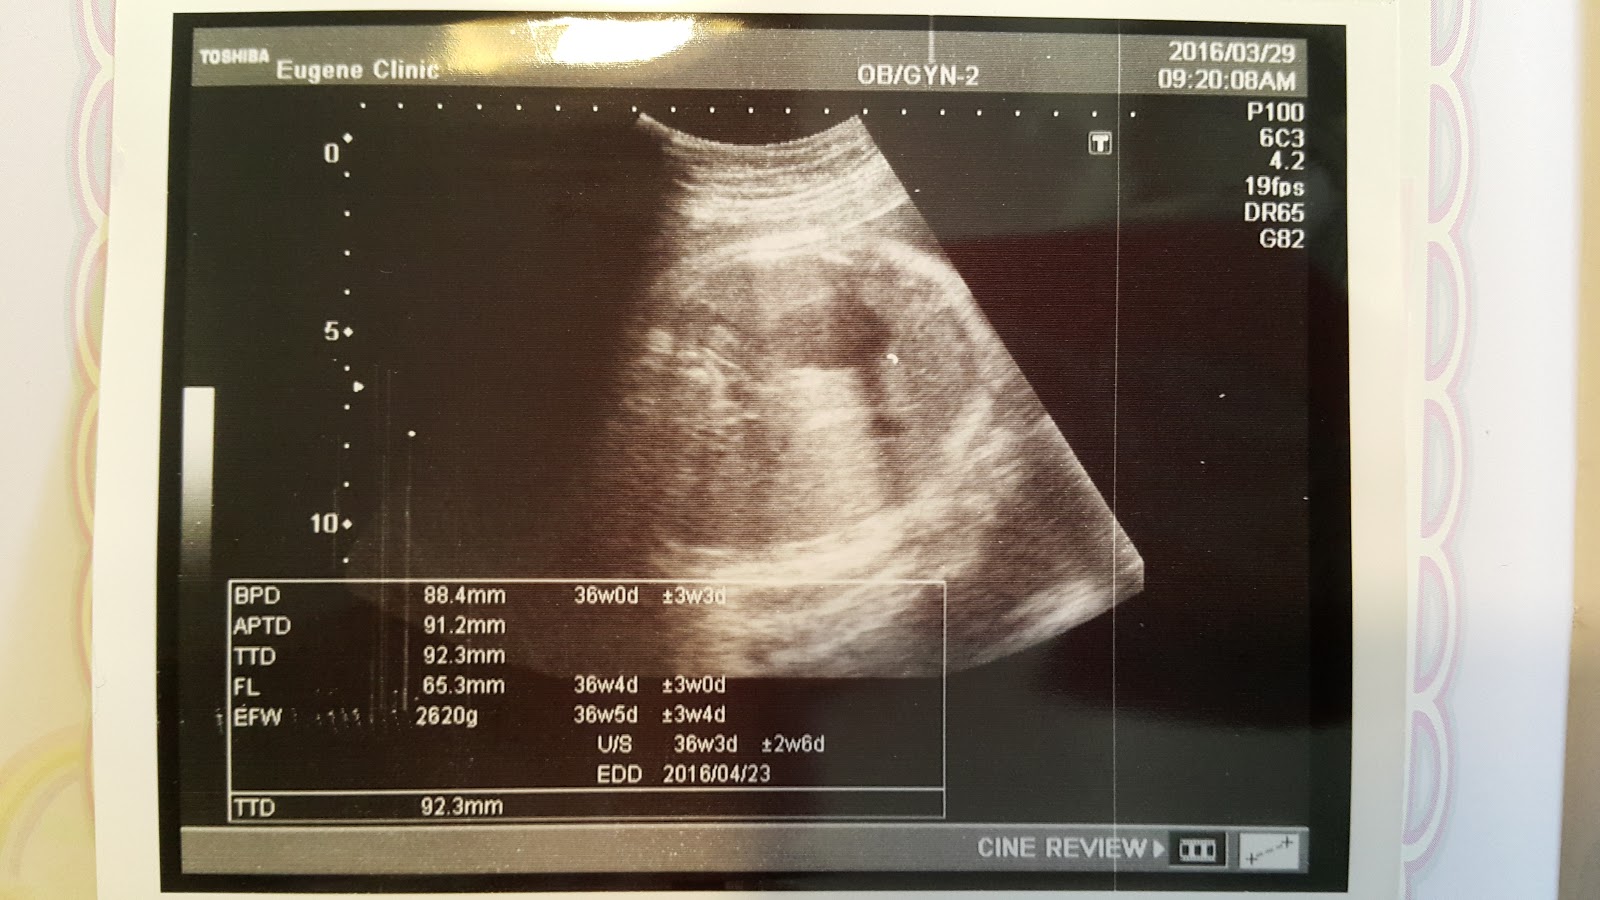

今天照超音波照了很多角度,幾乎把Haru看光光:P

胎位正常、羊水足夠、心跳也很有力

目前Haru的體重已經來到2620g,比上週多了160g